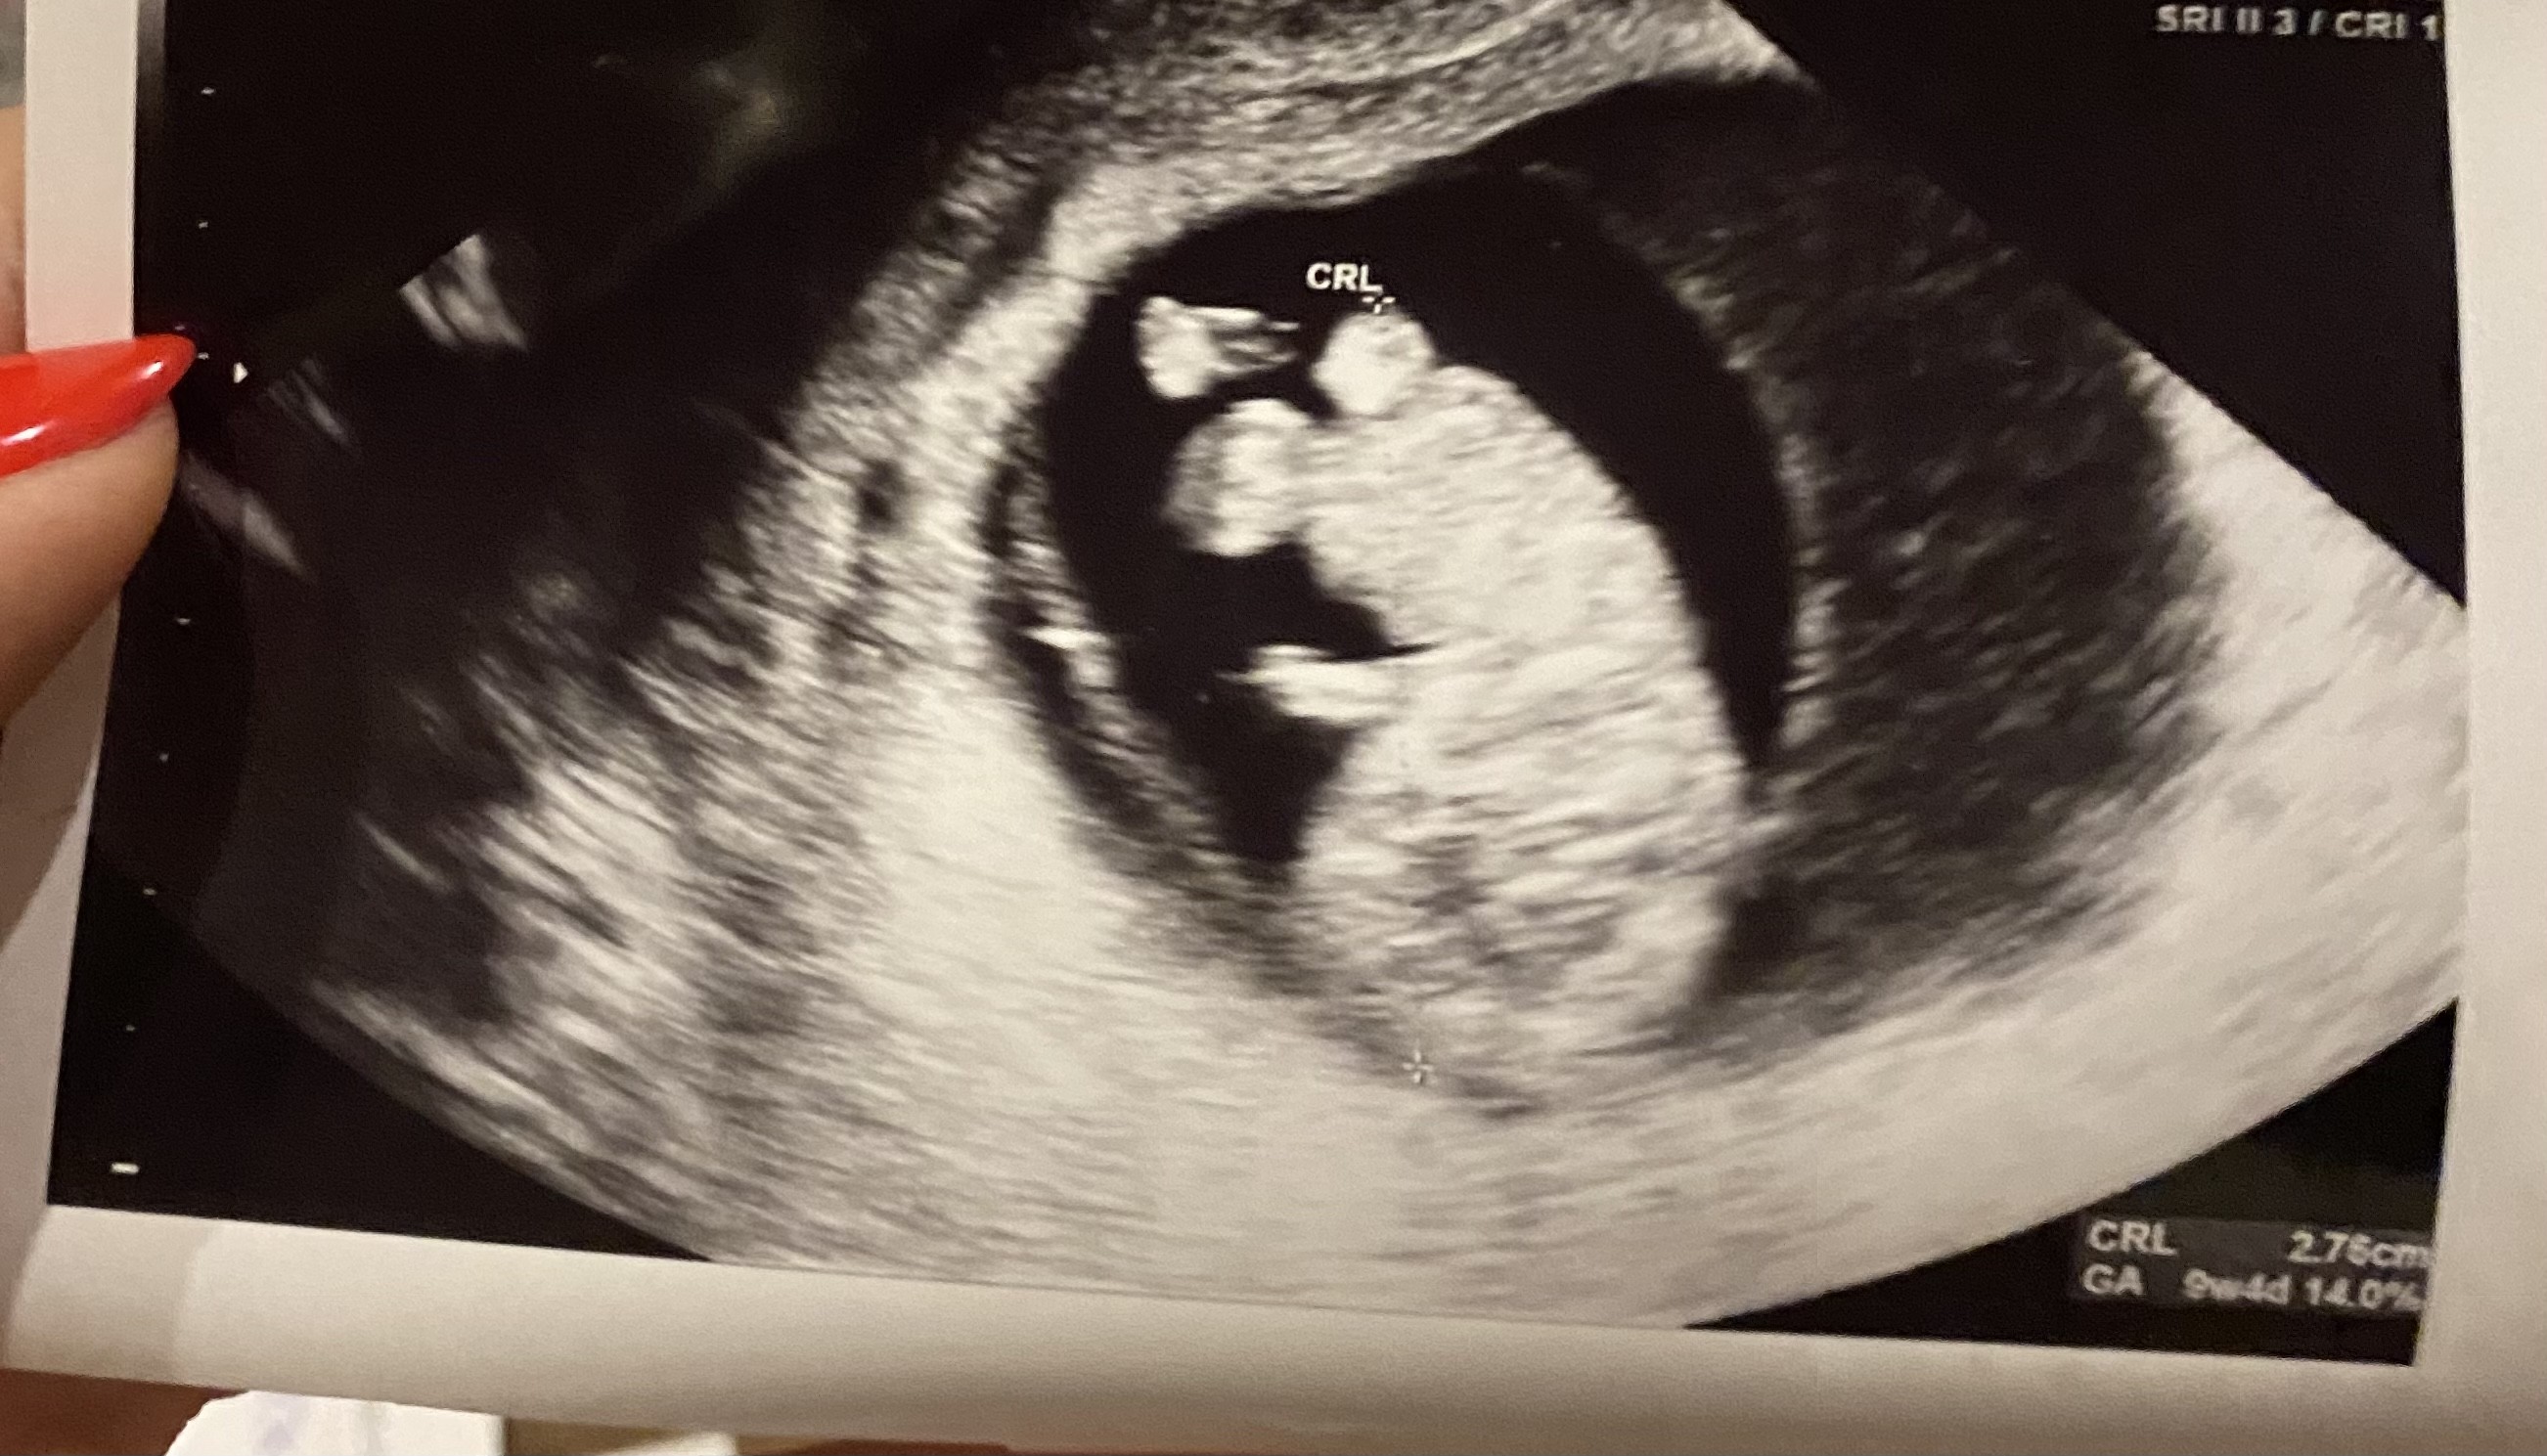

U mnie wszystko bardzo dobrze bobas rośnie załączam zdjęcie , następna wizyta 9 stycznia dostałam skierowanie na papa a usg bd mi robić koja prowadząca tylko dziwnie jakoś bo dzisiaj wg apki 9+6 , a ty tym zdj które wstawiam mam lewy górny róg ga9w4d , a prawy dolny jest 9w4d.

A na drugim zdj pisze jakieś 9w5d , ktoś pomoże rozwiązać ta zagadkę?😅😠

Moim zdaniem z miesiączki wypada 9w6d

A z usg wypada 9w5d